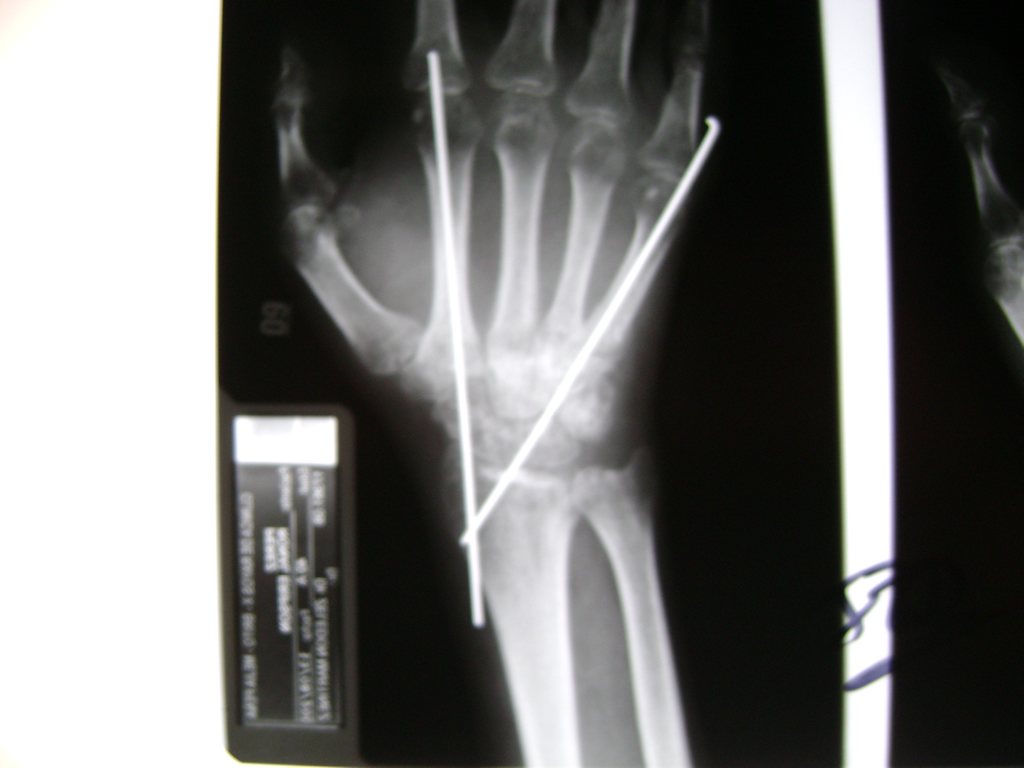

Los procedimientos más comunes en cirugía de la mano son aquellos destinados a reparar traumatismos, incluyendo lesiones de tendones, nervios, vasos sanguíneos, y articulaciones; huesos fracturados; y quemaduras, cortes, y otros daños de la piel.